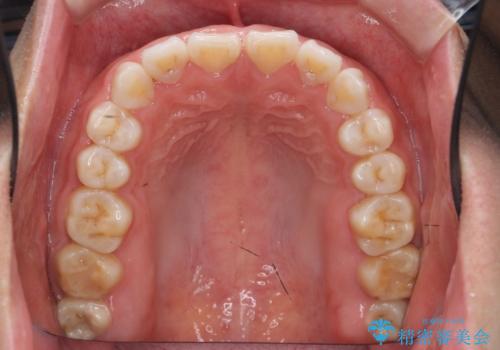

インビザライン 気になるすきっ歯の改善

- 上下顎前歯部の空隙が気になるので治したいと当院にいらっしゃった方の症例です。

非抜歯、インビザラインによる矯正治療により歯と歯の隙間および前歯の上下の隙間を閉じ切りました。